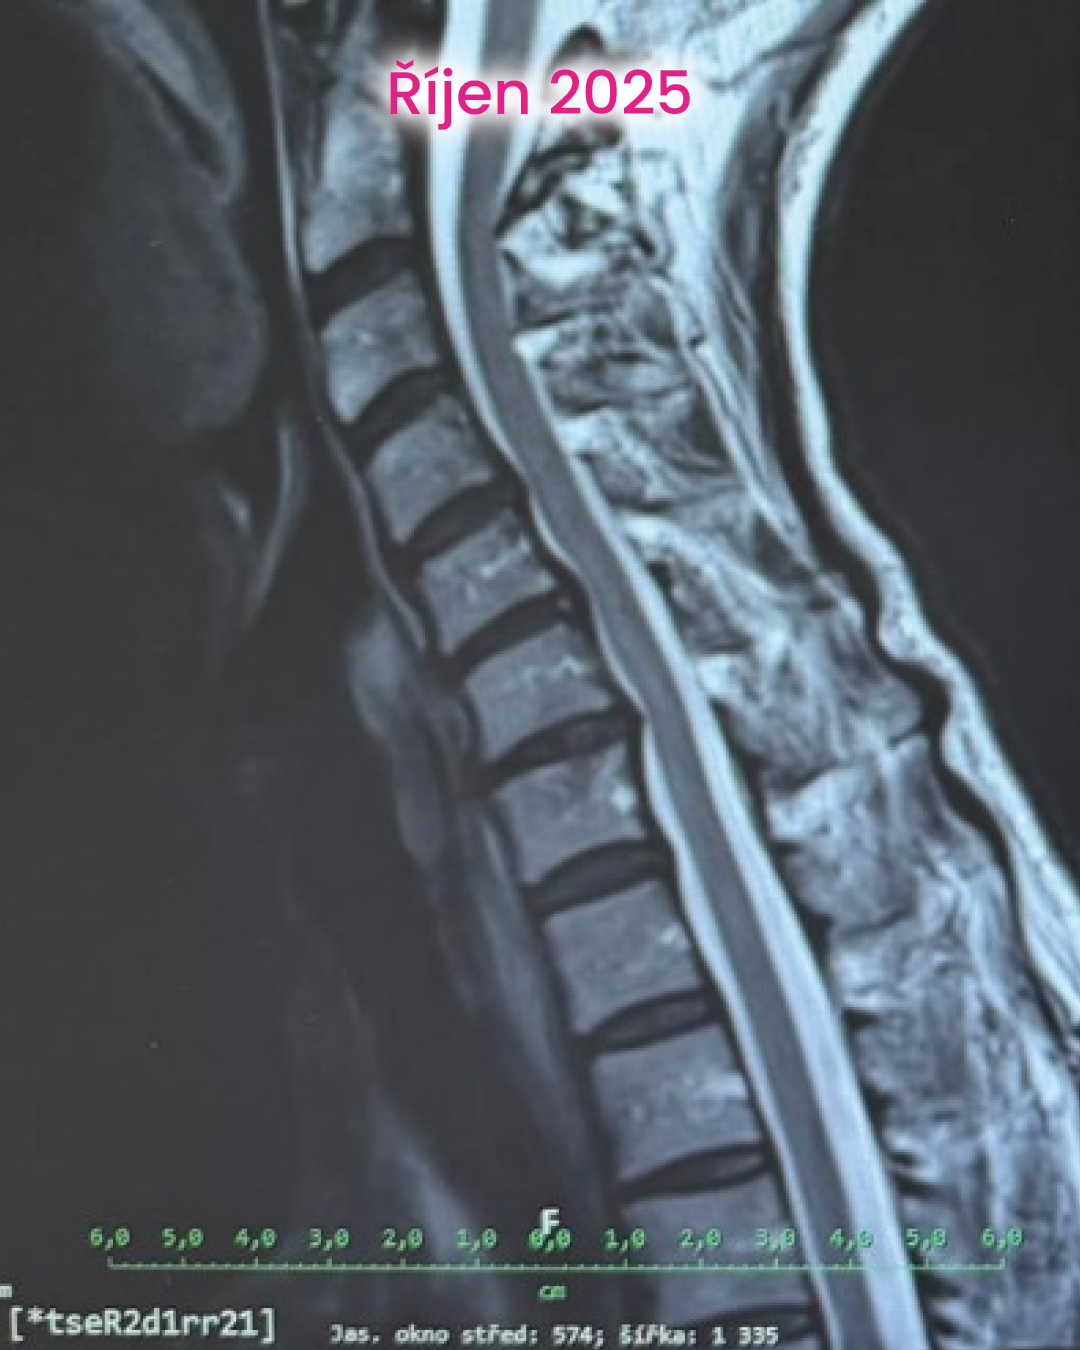

První změny přišly překvapivě rychle. Bolest začala ustupovat, brnění se objevovalo méně a spánek se postupně vracel. Přidaly jsme nordic walking pod vedením instruktora. V září byla klientka bez bolesti, spala bez přerušení a fungovala normálně v pohybu i běžném životě. V prosinci už si zase mohla nazout skialpové bot, skialpy a vyrazit na krátký trek.

Zelené zóny převažují a zatížení je rozložené mnohem rovnoměrněji. Reflexní mapa ukazuje klidnější nervový systém. A svaly už nefungují v režimu neustálé kompenzace. To zásadní ale není na obrázcích. Největší změna je v tom, že tělo přestalo bojovat samo proti sobě.

V tomhle případě ale tělo dostalo šanci – a využilo ji.